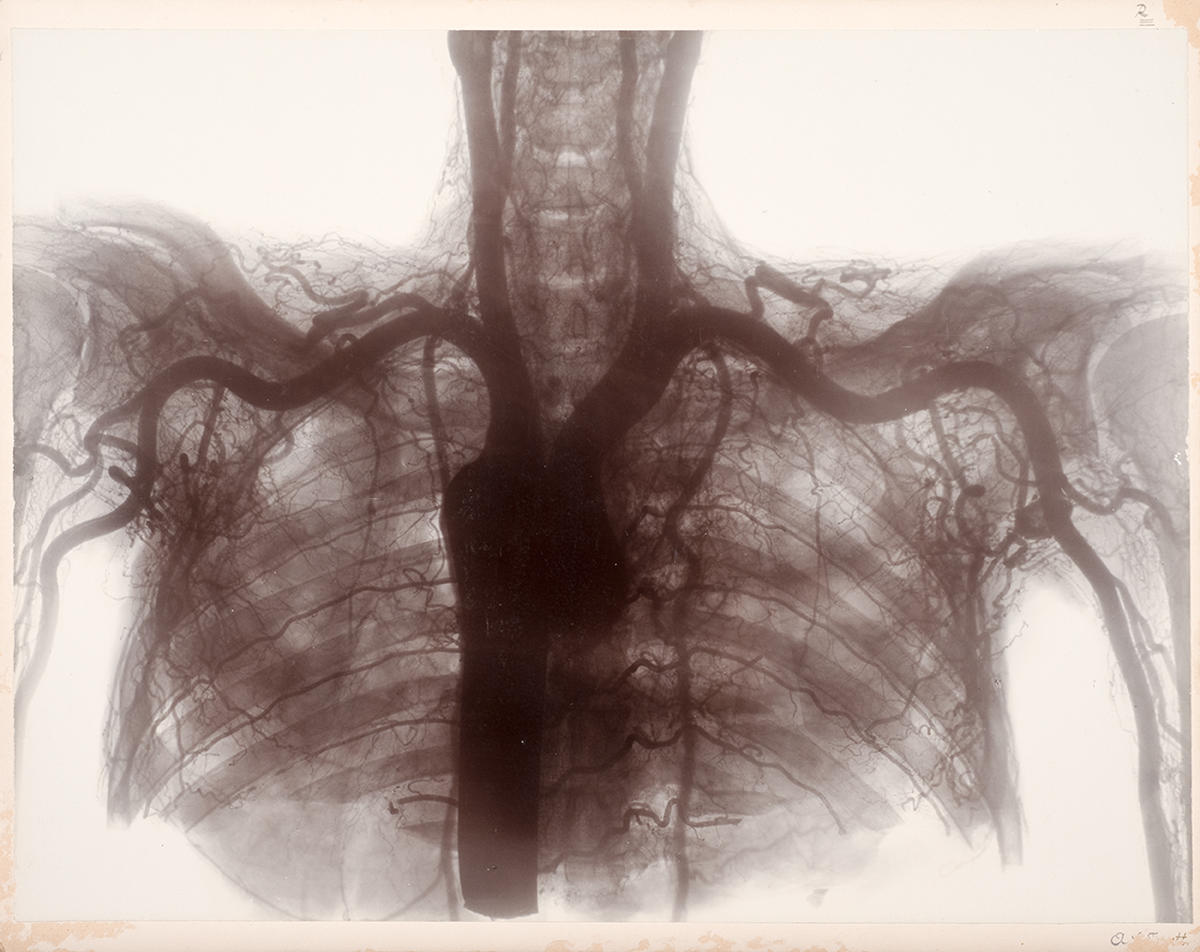

From collections.mdhs.unimelb.edu.au

Stereo skiagram of the vessels of the upper part of thorax and shoulder Chest Skiagram Meaning Not all chest pains are symptoms of a. The meaning of skiagram is a figure formed by shading in the outline of a shadow. Soft tissues including the left breast shadow is symmetrical and normal. (3) chest skiagram of our case showed a large homogenous density lesion in right hemithorax. If you experience momentary, localized or pinpoint chest pain that. Chest Skiagram Meaning.